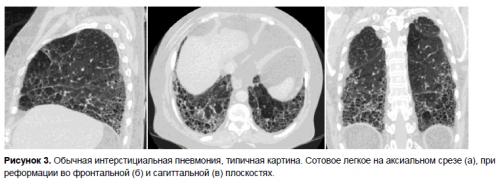

Рисунок 1. Фиброз легких. Источник: МедПортал

Грубые рубцовые волокна обладают низкой эластичностью (рис. 1). Они сдавливают бронхи, нарушают способность легких растягиваться при вдохе и сжиматься при выдохе. В результате этого нарушается дыхательная функция легких — процесс прохождения через альвеолярные стенки углекислого газа и кислорода.